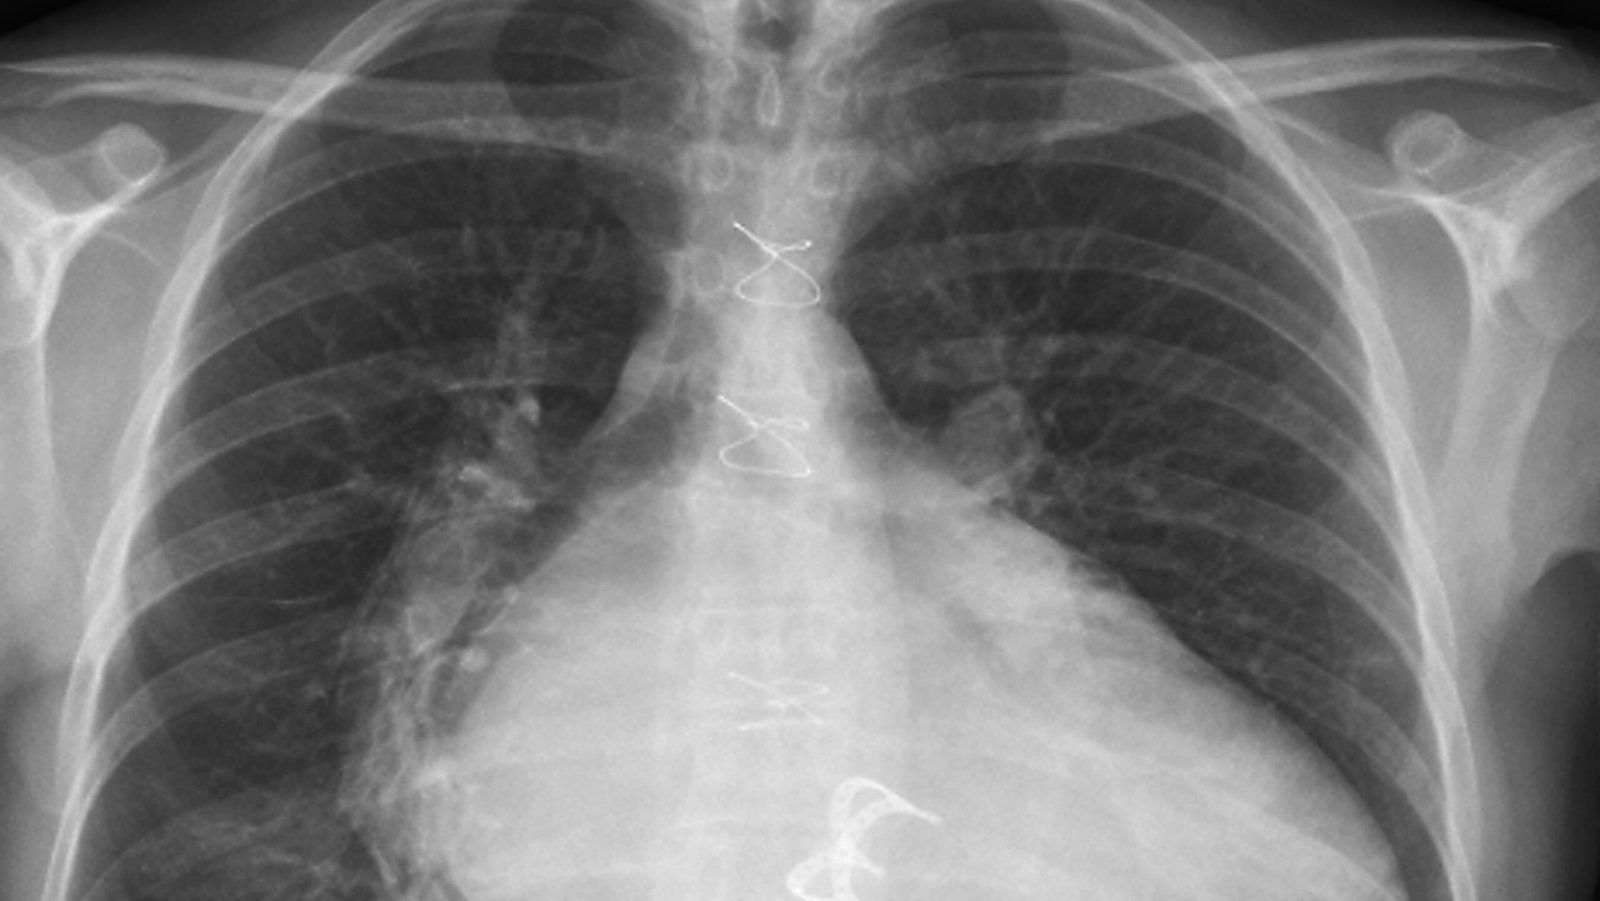

La Justicia falló a favor de un ciudadano de la provincia de La Pampa que demandó a una compañía de seguros por mala praxis. ¿El hecho que desencadenó la denuncia? Una operación ante la sospecha de un tumor,el cual en realidad eran una gasas que salieron en las últimas radiografías. Estas fueron dejadas por médicos en su interior durante una cirugía de válvula del corazón.

Hace más de dos años, el demandante debió ser sometido a una operación de válvula de corazón. Al detectarse el supuesto tumor, o quiste hidatídico, en otro establecimiento médico, tomaron la decisión de llevar a cabo una nueva cirugía. Sin embargo, al momento de llegar a la zona en cuestión, se toparon con, lo que la ley denominó, un “oblito olvidado”.